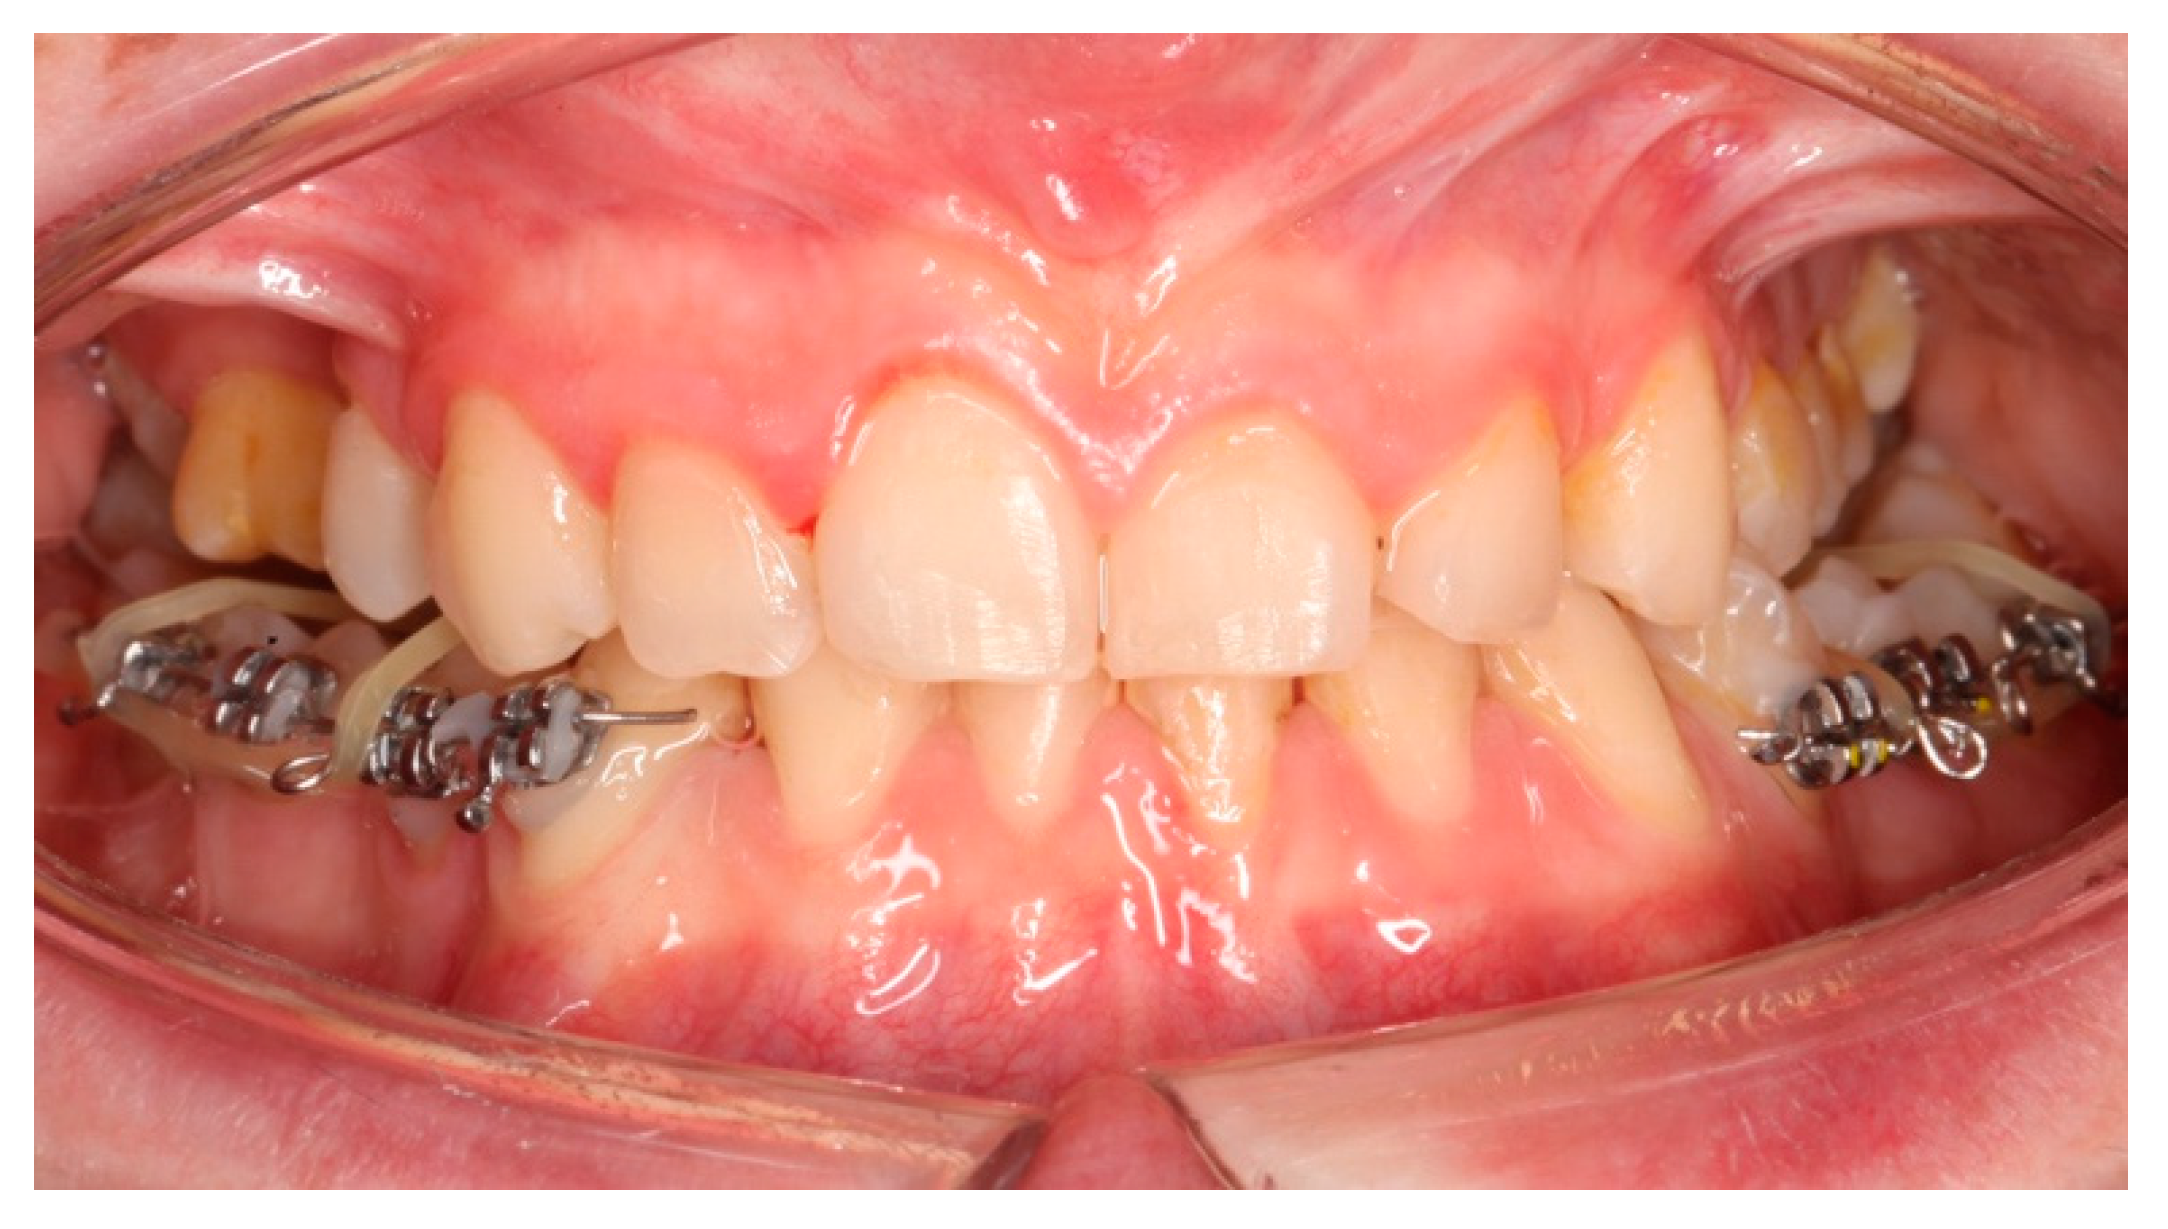

In June 2019, the objectives of the pre-surgical orthodontic treatment were considerably achieved: the arches were leveled, the teeth aligned, and the dental compensations of the third skeletal class had been removed. The pre-surgical diagnostic records were sent (Figure 2a–d) to the maxillofacial equip. Kobayashi ligatures were placed all over the teeth to prepare the patient for surgery.

Figure 2. a: antero-posterior projection of the CBCT. b: lateral-lateral projection of the CBCT. c: panoramic projection of the CBCT. d: frontal intraoral photograph. Kobayashi ligatures have been placed.